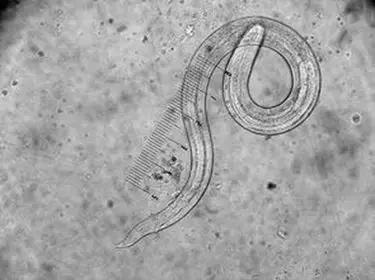

它的名字就叫——蛲虫。

蛲虫

有50%的可怜人在他长长的一生中可能会被蛲虫所扰。蛲虫一般喜欢住在我们肠道的末端,而要对我们身体产生影响,小蛲虫(幼虫)必须在小肠里孵化,变成成虫后来到大肠,给感染它的人捣乱。

在回肠和盲肠的交接处,长10mm的雌虫和长3mm的雄虫一通“翻云覆雨”,蛲虫爸爸奉献完毕很快就会死亡而被排出体外,而雌虫则带着艰巨的使命,怀着它的宝宝开始向菊花移动。

等我们休息睡觉时,肛门括约肌比较松~弛~,蛲虫妈妈就会爬出肛门外将它的宝宝(虫卵)产在菊花周围,每一只雌虫可以产下约10,000~15,000虫卵。

蛲虫感染虽然在儿童中发生率最高,但其实各个年龄段的人都有感染的可能。雌蛲虫一般能活1个月,很少超过2个月。